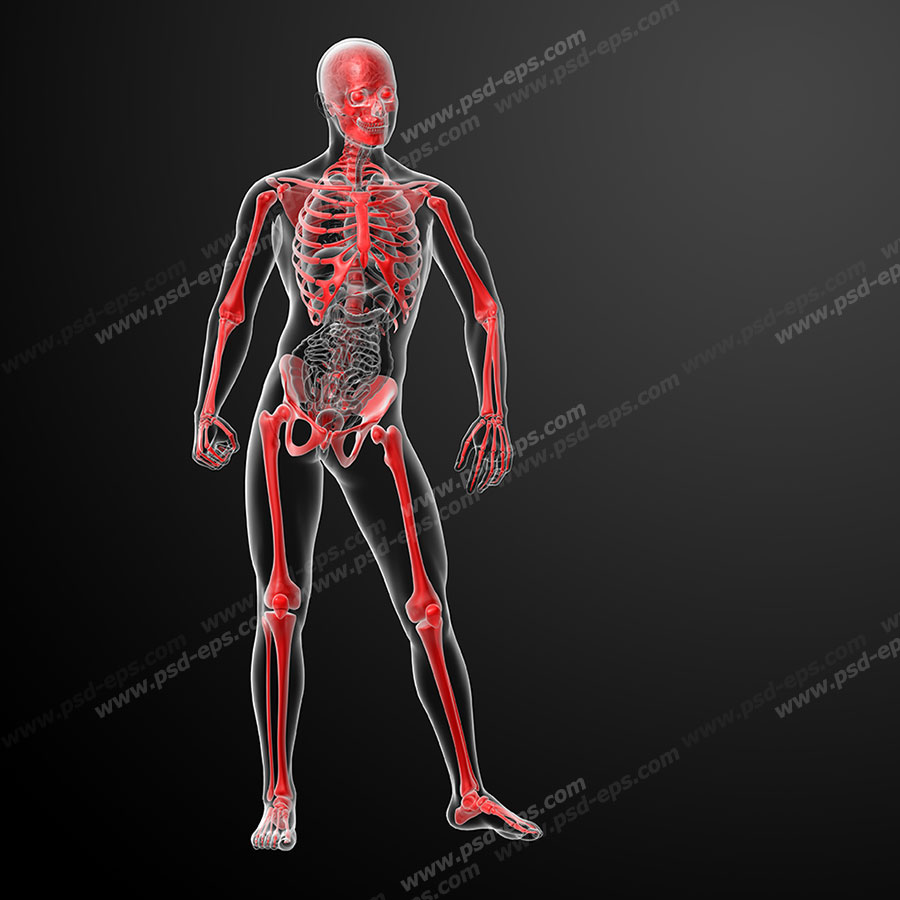

عکس اسکلت بدن انسان با کیفیت. عکس اسکلت عکس اسکلت برای پروفایل عکس اسکلت انسان عکس اسکلت خفن عکس اسکلت بدن انسان با کیفیت عکس اسکلت بدن انسان عکس اسکلت ترسناک عکس اسکلت فانتزی عکس اسکلت فانتزی دخترانه پرچم عکس اسکلت. عکس با کیفیت اسکلت داخلی انسان و درد و گرفتگی در ناحیه استخوان زانو ویژه استفاده در امور تبلیغاتی و تجاری طراحی کاتالوگ بروشور و تراکت با موضوع پزشکی فیزیوتراپی ارتوپد دکتر روماتیسم فیریوتراپ طب فیزیکی. عکس اسکلت بدن انسان زن و مرد آناتومی ساتین 16 سپتامبر 2017. اسکلت داربست بدن است تمام قسمت های بدن روی اسکلت قرارگرفته اند بدن انسان از ۲۰۶ قطعه استخوان تشکیل شده است این استخوان ها طوری با نظم کنار هم قرار گرفته اند که انسان را قادر می سازد حرکات دقیقی داشته باشد.

اسکلت جمجمه و گردن انسان ستون فقرات آناتومی اسکلت جمجمه و گردن انسان ستون فقرات آناتومی تصویر با کیفیت را از لینک زیر می توانید دانلود کنید. ۱ مطلب با کلمه ی کلیدی عکس اسکلت بدن انسان با کیفیت ثبت شده است گالری نسیم جدید ترین و با کیفیت ترین عکس های مناسبتی. عکس با کیفیت آناتومی اسکلت بدن انسان و درد و دیسک در قسمت مهره های ستون فقرات کمر ویژه استفاده در امور تبلیغاتی و تجاری طراحی کاتالوگ بروشور و تراکت با موضوع بیمارستان ها و کلینیک ها و درمانگاه ها و مطب ها پزشکان و.